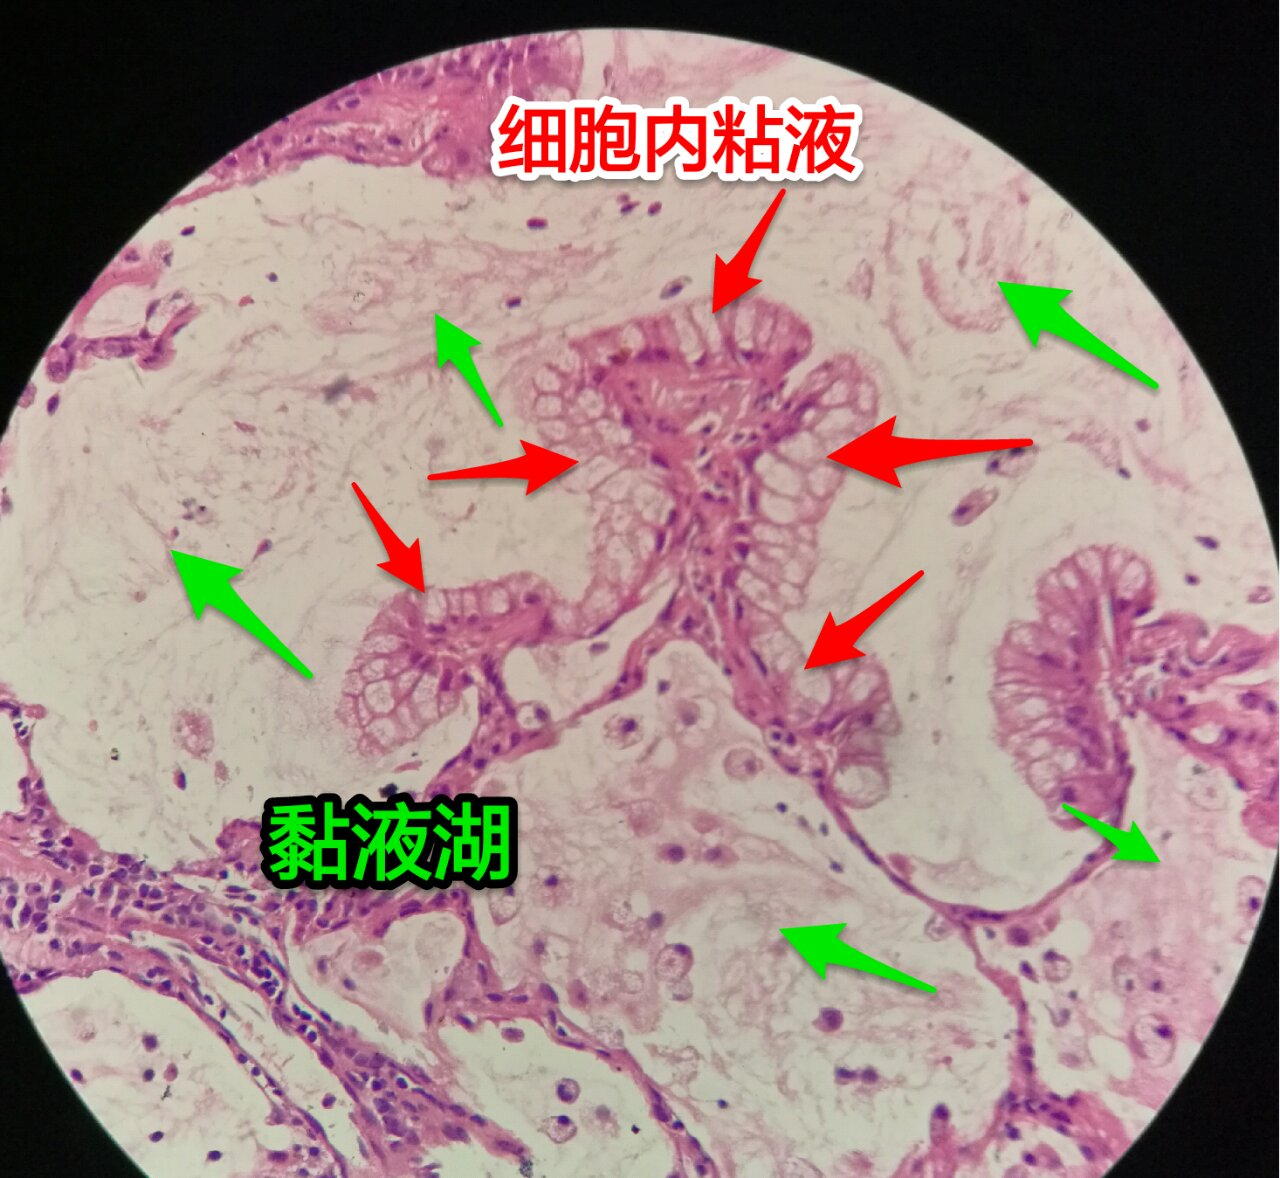

细胞内外含较多粘液

粘液型腺癌,细胞内粘液多,有点儿像支气管的粘液腺

细胞外粘液湖

细胞内白颜色区是粘液,细胞外洋流样的也是粘液(湖)

黏液湖里可以飘着一些细胞,吞噬细胞及肿瘤细胞。

粘液型腺癌的肿瘤细胞排列整齐,核位于基底,细胞呈柱状。